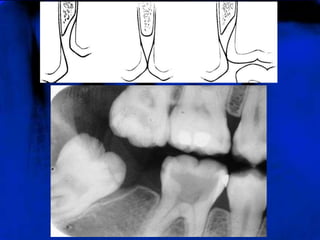

LÂMINA DURA (RO)Representa a porção da parede do alvéolo onde se inserem as extremidades externas das fibras periodontais. Apresenta-se radiograficamente como uma linha radiopaca fina que se continua com as cristas ósseas alveolares.

LÂMINA DURA (RO)

CRISTA ÓSSEA ALVEOLAR (RO)A crista alveolar apresenta-se como uma linha radiopaca contínua, delgada e lisa, cobrindo, sem solução de continuidade, o osso esponjoso contido nas cristas e passando de um dente ao outro, sem interrupção.

CRISTA ÓSSEA ALVEOLAR (RO)

LÂMINA DURA (RO)Representaa porção da parede do alvéolo onde se inserem as extremidades externas das fibras periodontais. Apresenta-se radiograficamente como uma linha radiopaca fina que se continua com as cristas ósseas alveolares.

CRISTA ÓSSEA ALVEOLAR(RO)A crista alveolar apresenta-se como uma linha radiopaca contínua, delgada e lisa, cobrindo, sem solução de continuidade, o osso esponjoso contido nas cristas e passando de um dente ao outro, sem interrupção.